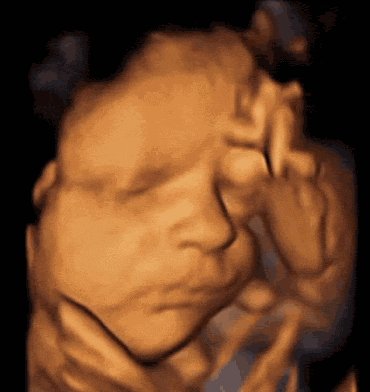

1.四维彩超的检查目的

通过四维超声检查,能够准确反映出胎儿生长发育情况,多角度、多方位进行胎儿异常评估。包括先天疾病。如胎儿唇腭裂、四肢发育畸形、脑膜膨出、脊柱裂、腹壁裂等先天畸形。

▶查看胎宝宝的活动

可以检查到胎宝宝在宫内是否缺氧,肢体运动、胎儿的吞咽动作等,能够很好地看到胎儿在孕妈妈体内的活动状况,说不定还可能看见宝宝做鬼脸、伸舌头哦。